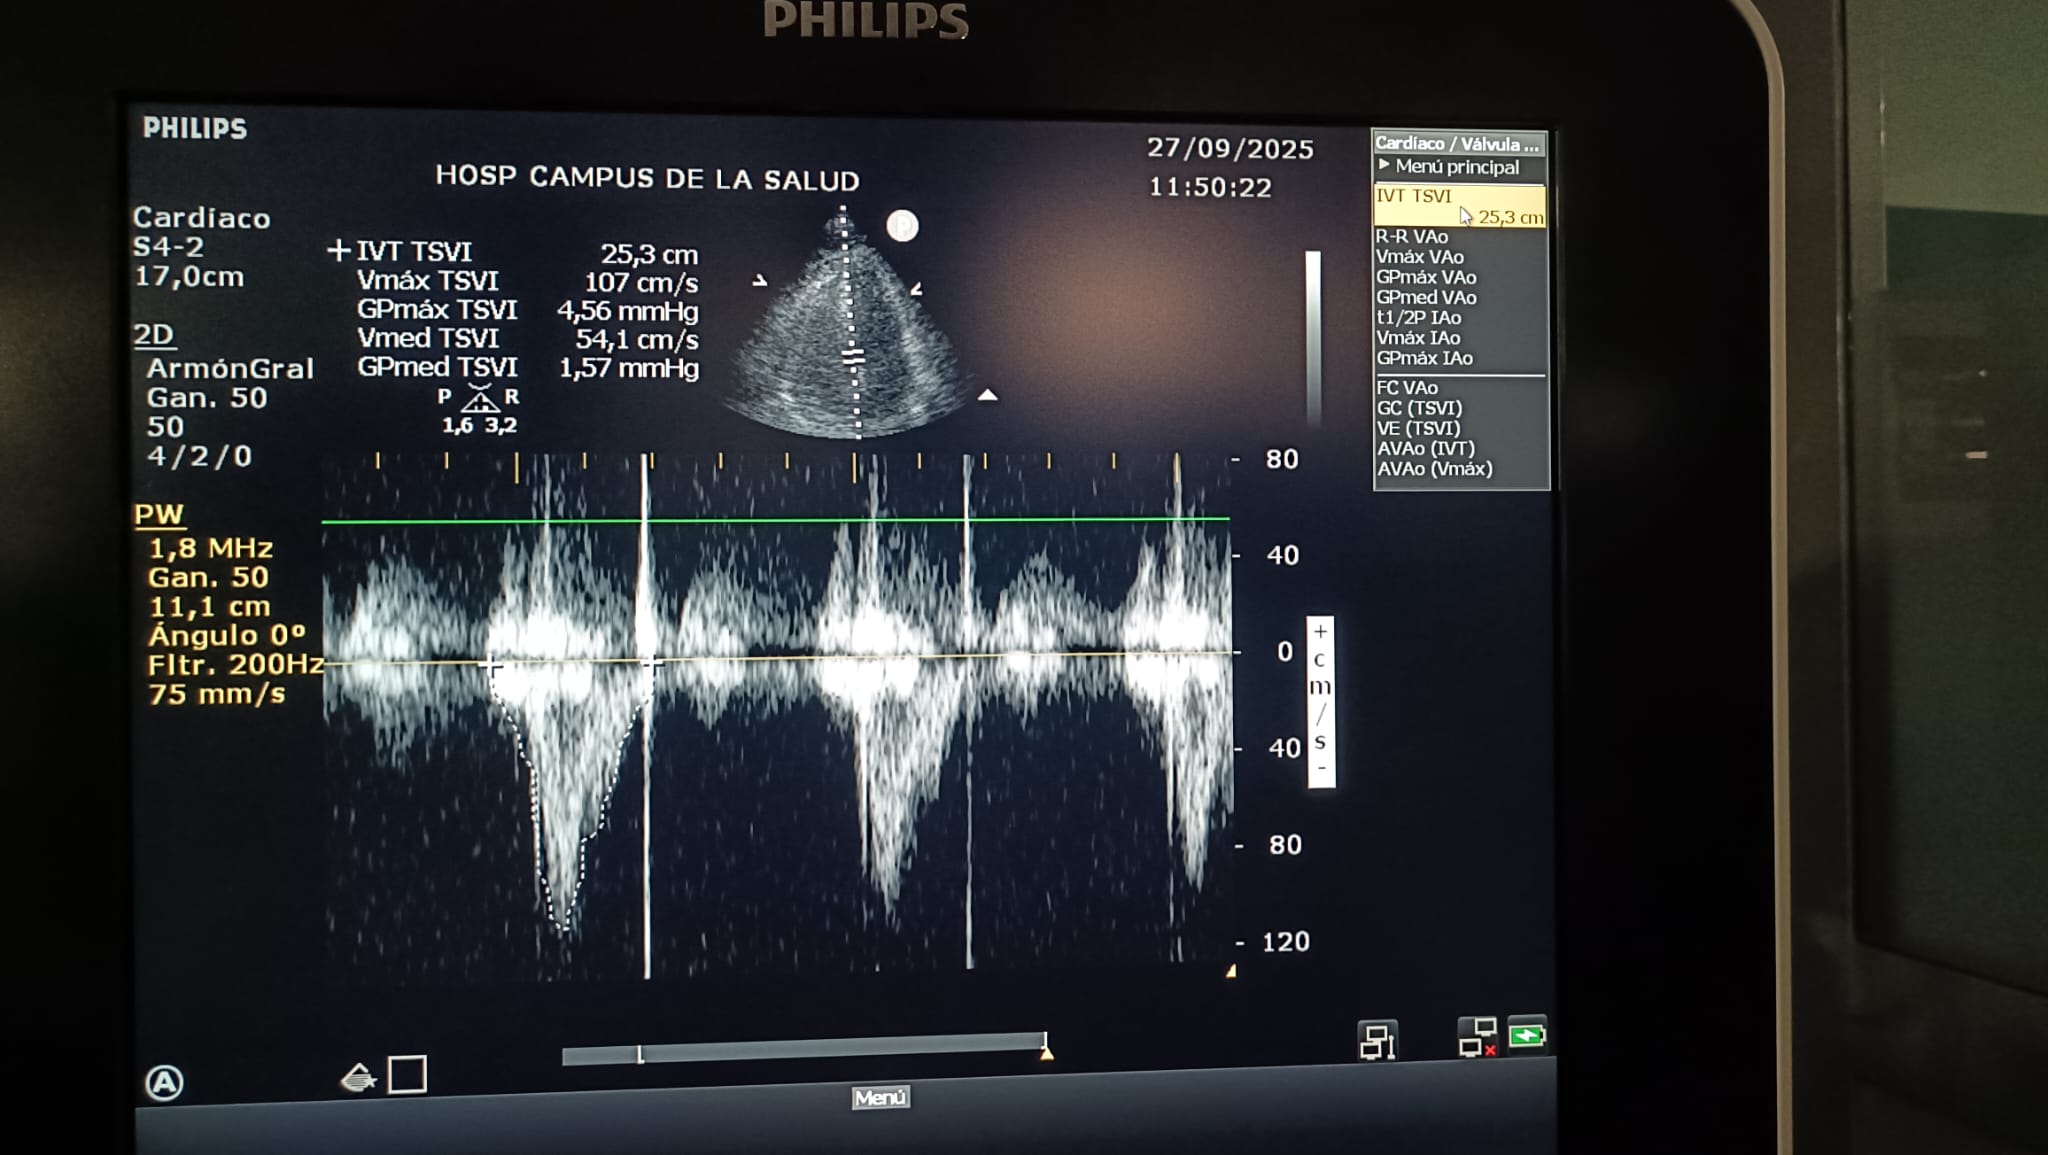

IVT: 25.3